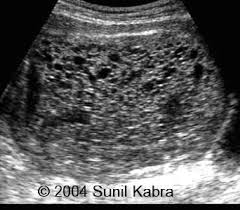

On Radiology Molar Pregnancy Snow White Appearance On Ultrasound

Ultrasound remains the radiological investigation of choice for initial.

The latter four entities are referred to as gestational trophoblastic neoplasia GTN. A common characteristic of all gestational trophoblastic disease is an abnormal proliferation of trophoblast but different components predominate in different tumors. Ultrasound remains the radiological investigation of choice for initial. Gestational trophoblastic neoplasia GTN encompasses a broad spectrum of placental lesions from the pre-malignant hydatidiform mole complete and partial through to the malignant invasive mole choriocarcinoma and rare placental site trophoblastic tumour PSTT. The latter four entities are referred to as gestational trophoblastic neoplasia GTN. There are several histologically distinct types of GTD that range from premalignant complete and partial hydatidiform moles HMs to malignant diseases also known as gestational trophoblastic. Ultrasound in the Diagnosis and Management of GTN Gestational trophoblastic neoplasia GTN includes invasive mole choriocarcinoma PSTT and ETT. Because it is an unusual and serious disease that affects women of reproductive age as well as because its appropriate treatment results in high cure rates it is crucial that radiologists be familiar with gestational trophoblastic disease in order to facilitate its early diagnosis and to ensure appropriate follow-up imaging. Gestational trophoblastic disease GTD is a spectrum of both benign and malignant gestational tumors including hydatidiform mole complete and partial invasive mole Choriocarcinoma placental site trophoblastic tumor and epithelioid trophoblastic tumor.